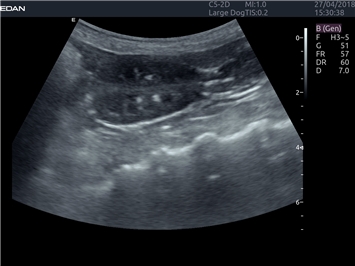

EDAN Acclarix LX4 VET представляет собой профессиональную ультразвуковую систему, специально разработанную для ветеринарных исследований. Сочетание стабильности, высокой производительности и эффективности делает эту систему идеальным выбором для современной ветеринарной практики.

Адаптация для ветеринарной практики:

• Универсальные датчики для различных видов животных

• Специализированные предустановки для ветеринарных исследований

• Гибкие протоколы исследований

Области применения:

Система оптимально подходит для:

• Ветеринарных клиник

• Специализированных ветеринарных центров

• Животноводческих комплексов

• Конных клиник

• Научно-исследовательских ветеринарных учреждений